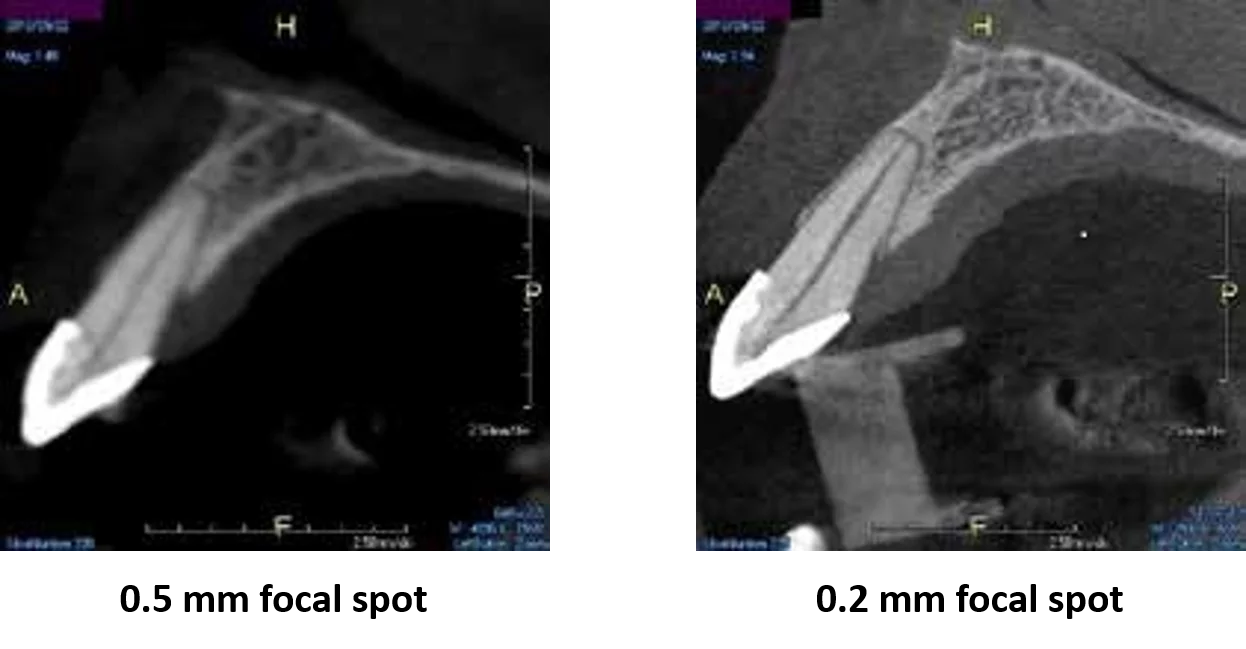

A 0.2 mm focal spot will allow you to spend less time convincing patients of your diagnosis and more time practicing dentistry.

Most cone beam systems either have a 0.5 mm or worse (larger focal spots equal less edge sharpness). The X-era focal spot is one of the smallest in the industry for a dental cone beam system. This not only means you and your staff can see more, but your patients can as well.